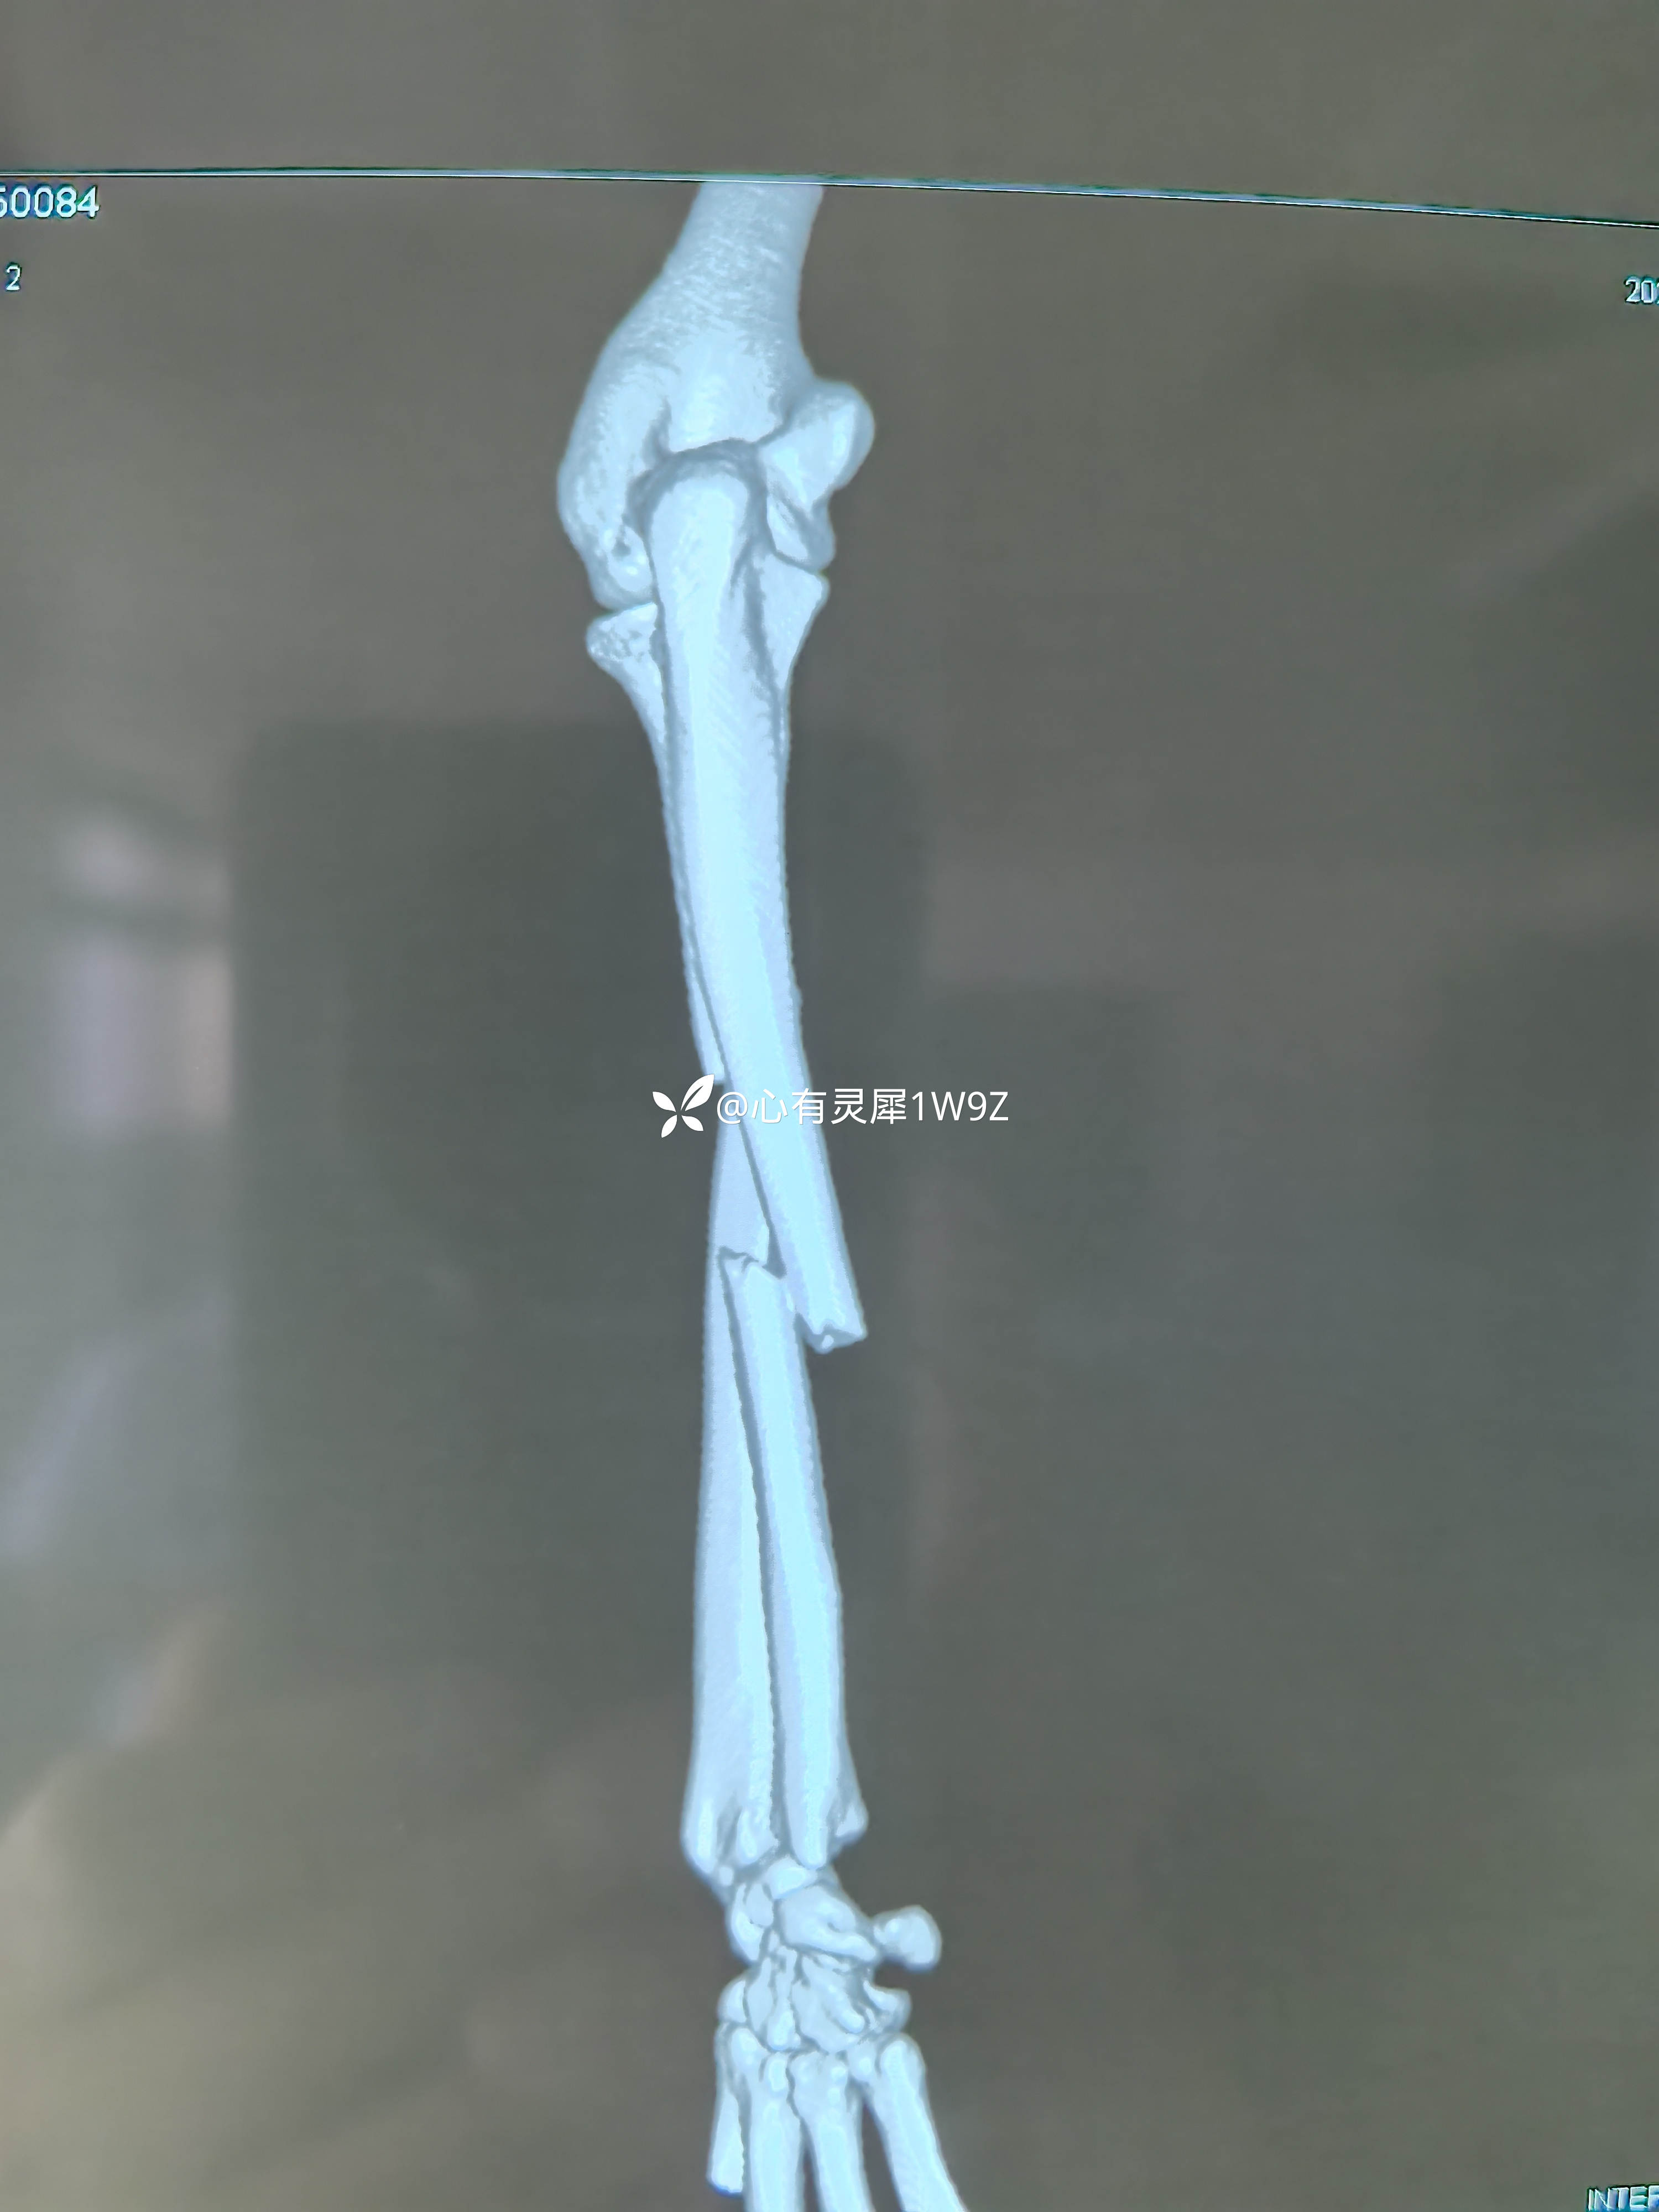

尺桡骨双骨折钢板内固定

【临床诊断】:左侧尺桡骨双骨折